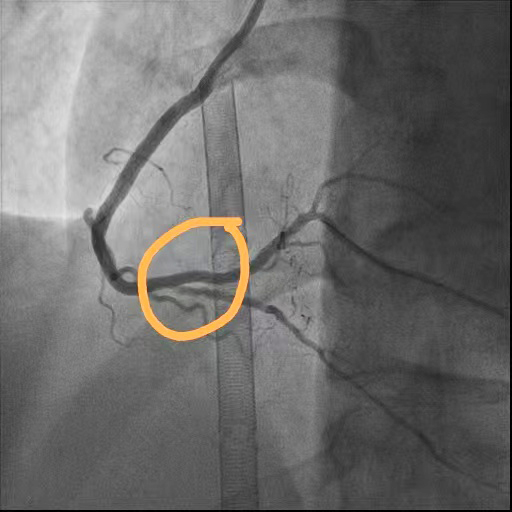

术后

回旋支狭窄解除

前降支闭塞段开通

右冠脉狭窄解除